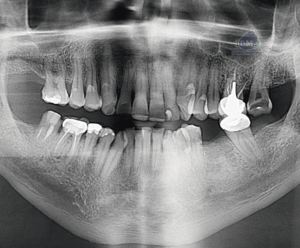

En la ampliación imagenológica con tomografía computarizada de haz cónico, a nivel del cuerpo mandibular derecho, se identifican forámenes accesorios adicionales al agujero mentoniano principal. Se observa un segundo agujero mentoniano de menor diámetro, ubicado superior al principal, con trayecto cefálico. Además, se identifica un tercer agujero mentoniano localizado en posición distal respecto al foramen principal.

Si bien las radiografías panorámicas continúan siendo útiles como primera aproximación diagnóstica, presentan limitaciones importantes debido a la superposición de estructuras, la posible distorsión de la imagen o la orientación del foramen, que puede ocultar su presencia. En este caso, los múltiples agujeros mentonianos del lado izquierdo no fueron evidenciados en la radiografía panorámica. La tomografía computarizada de haz cónico permitió identificarlos con precisión, demostrando su valor como herramienta indispensable para el diagnóstico detallado y la planificación quirúrgica, especialmente en la colocación de implantes en esta región (2).

En este contexto, la evaluación tridimensional se convierte en un recurso imprescindible, ya que permite visualizar con exactitud variaciones anatómicas que pasan desapercibidas en estudios bidimensionales. La correlación entre los hallazgos en tomografía y los antecedentes de fallas anestésicas previas en la zona puede orientar al clínico hacia la explicación de bloqueos ineficaces, minimizando riesgos y permitiendo un abordaje quirúrgico y anestésico más seguro y predecible.